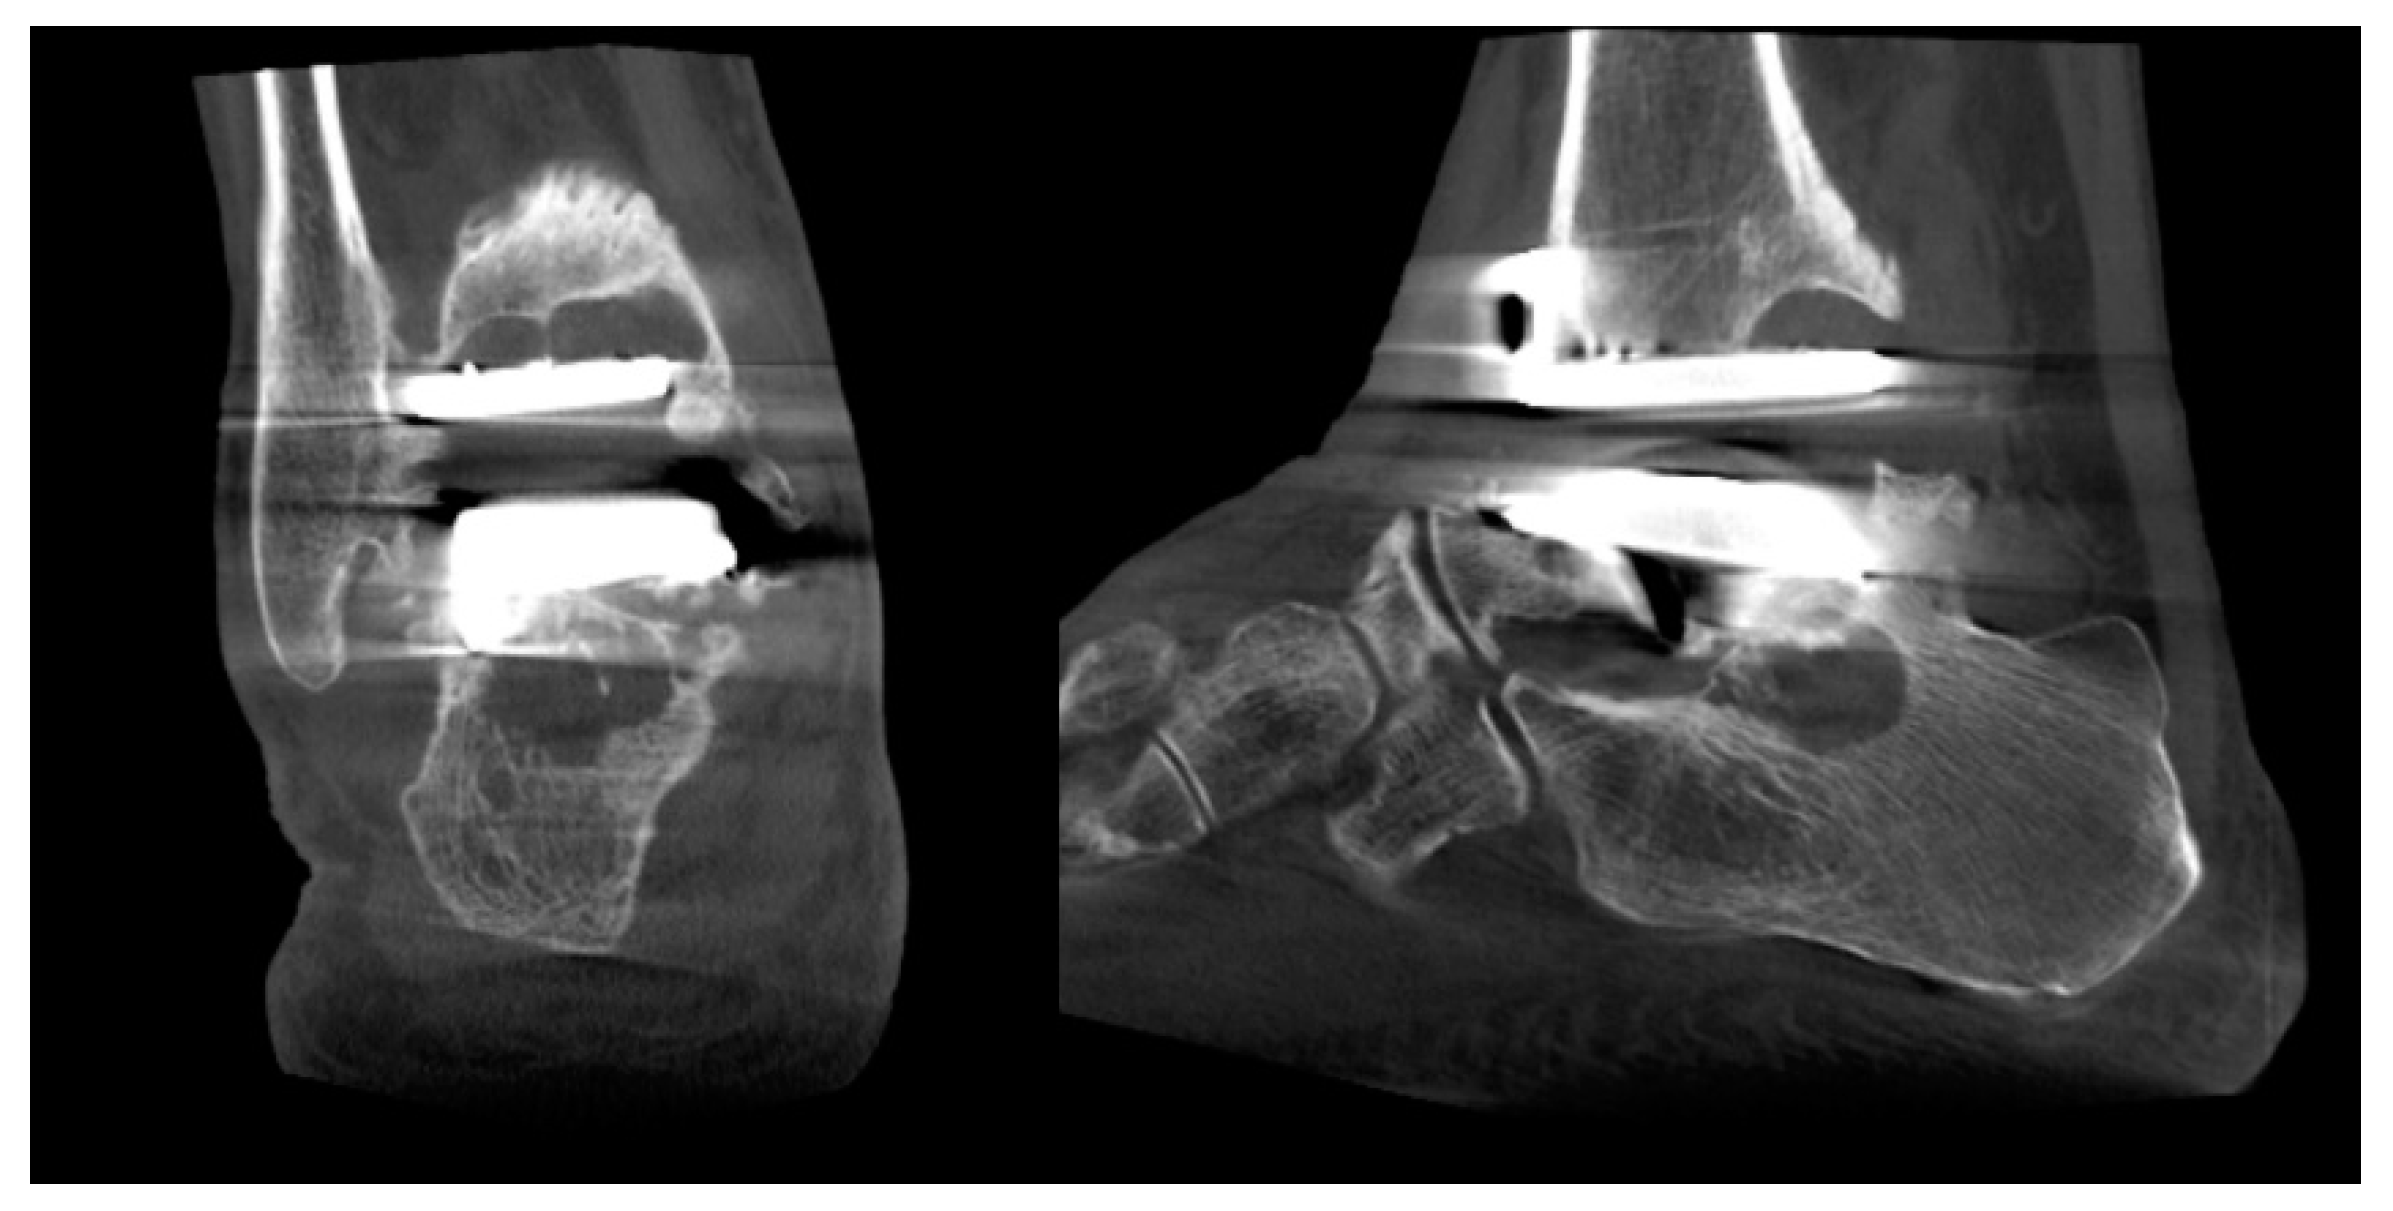

Ankle Replacement Surgery